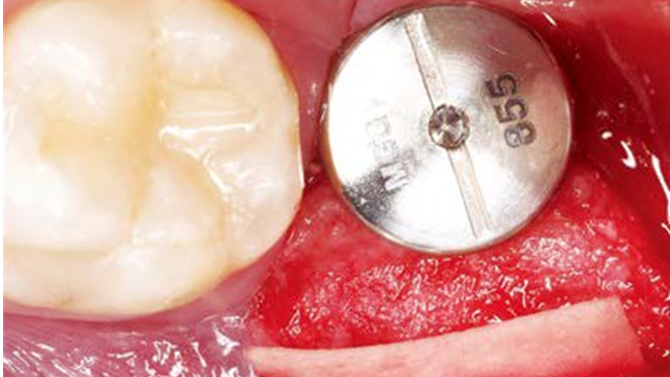

Clinical case: Bone filling into the bottom of deepest thread at 8.0mm AnyRidge fixture

- Courtesy of Dr. Kwang Bum Park -

Keywords

AnyRidge, Knifethread ,extraction socket, ,initial stability ,Allograft, ,osseointegratio ,Dr. Kwang Bum Park, , Mandibular, Single replacement, AnyRidge, Mega-oss,

Products used

Implant system-AnyRidge, Regeneration-Mega-Oss

“AnyRidge implant enables fast and stable

osseointegration at this extreme case of bone defect. ”